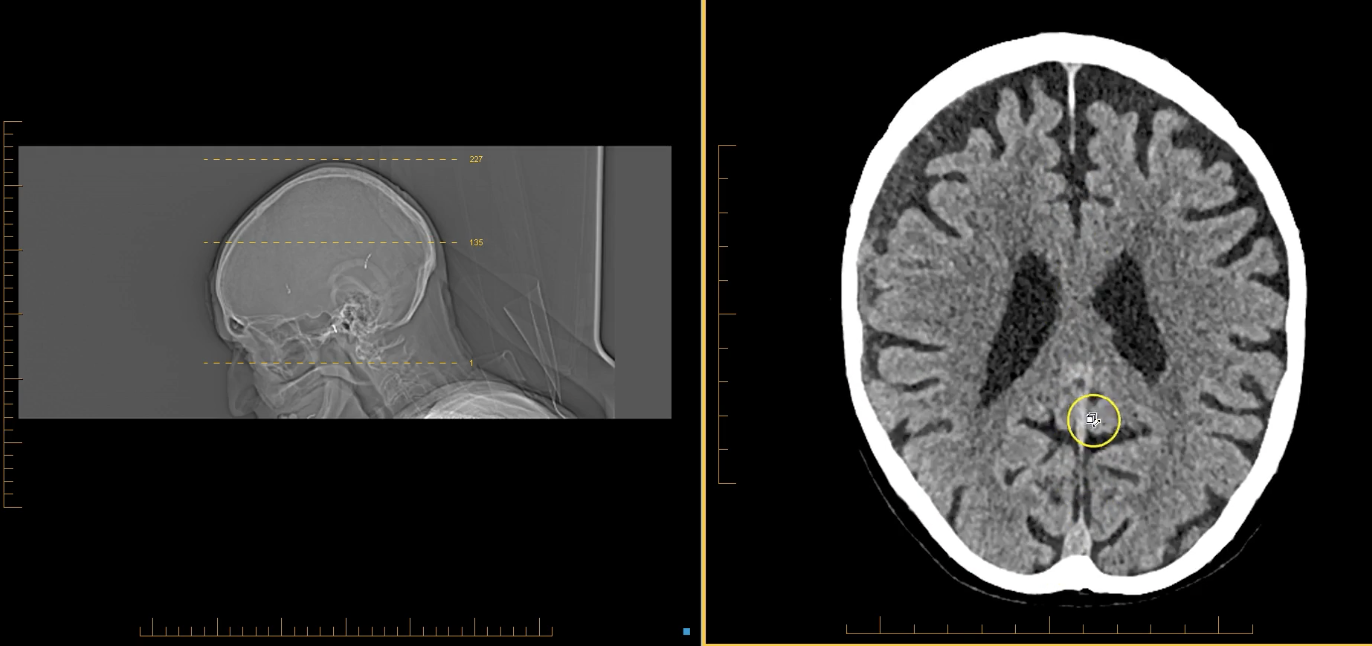

term image

lateral ventricles